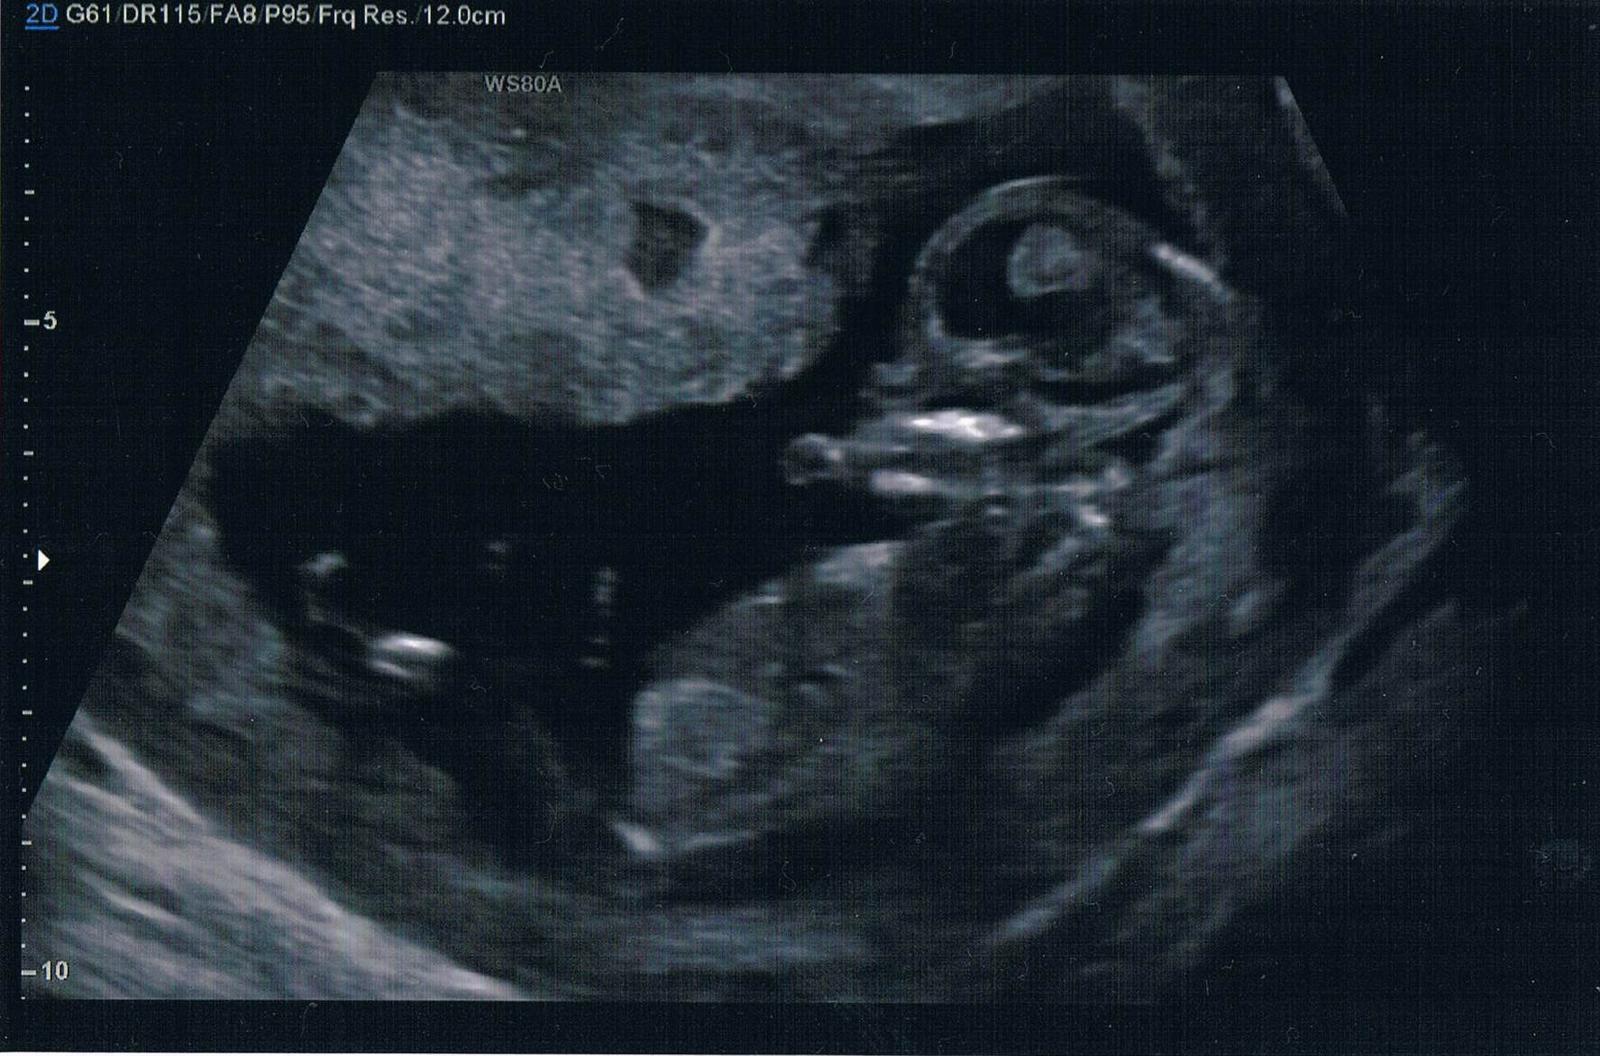

Je to holčička nebo chlapeček? Foto ultrazvuku

@arnicka Asi holčička bych rekla

Jestli jsem se dobre zorientovala, pripadne mi to na holcicku, nevim. A dr rekla co?